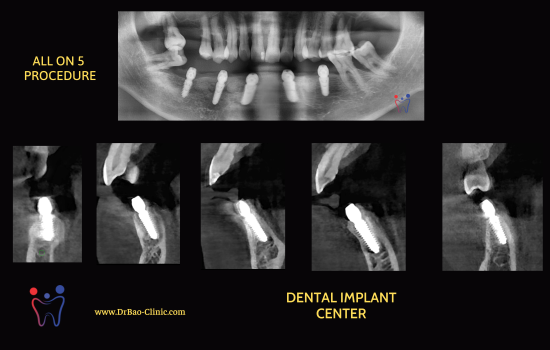

Phim XQuang sau phẫu thuật – Các implant được đặt đúng vị trí giúp tối ưu về chức năng và thẩm mỹ cũng như sự ổn định lâu dài của implant